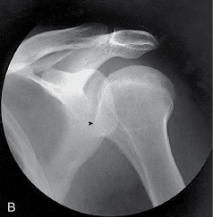

name the projection and rotational; label the part of the humerus the arrow is pointing to

AP internal, lesser tubercle